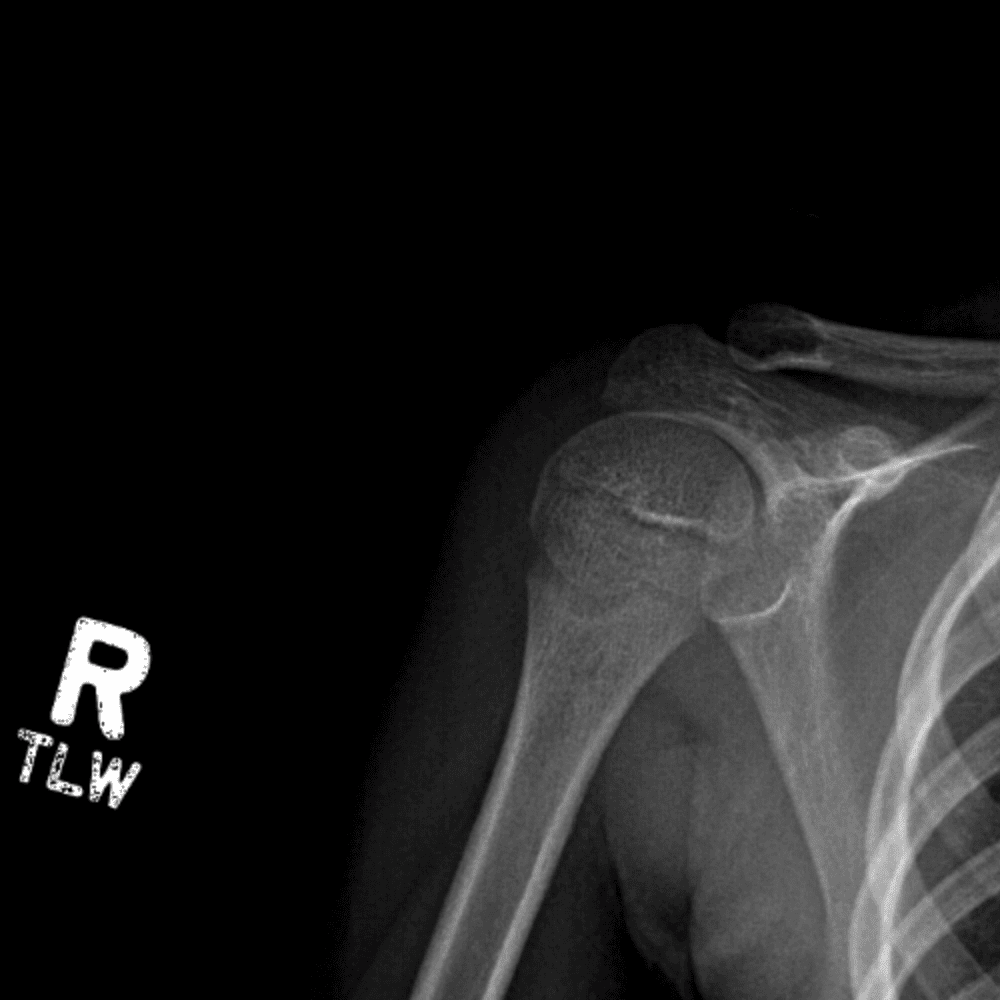

Simuliert den Dienst durch subtile oder schwierige Fälle und einige Normalbefunde.

30 Fälle